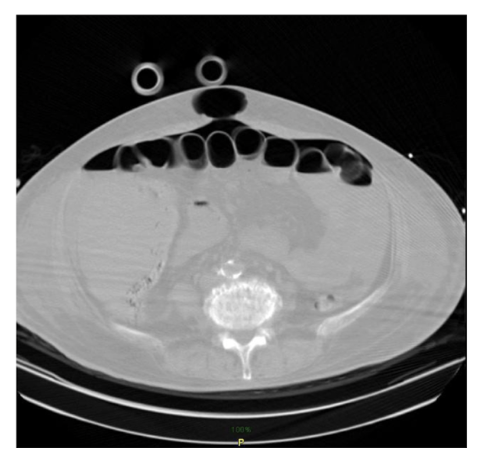

• Ascites: abnormal

collection of

intraperitoneal fluid

• Evidenced by the fluid within the recesses of

peritoneal cavity